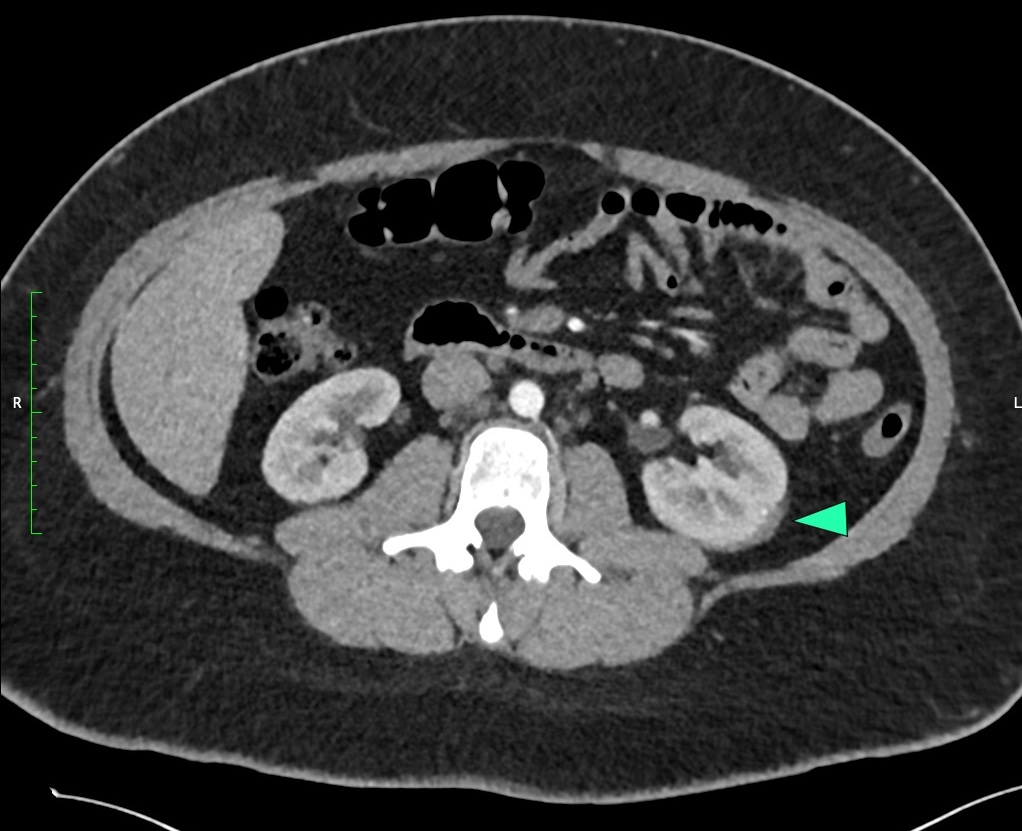

A l’examen clinique, le patient est normotendu, normocarde et eupnéique et présente une douleur à l’ébranlement de la loge rénale gauche. Le CT-scanner throraco-abdominal met en évidence un très discret hématome périrénale gauche, sans fracture rénale associée ni lésion ou de dilatation pyélocalicielle.

Ce patient présente un hématome isolé du rein gauche (flèche verte) de grade 1 selon l’AAST (1).